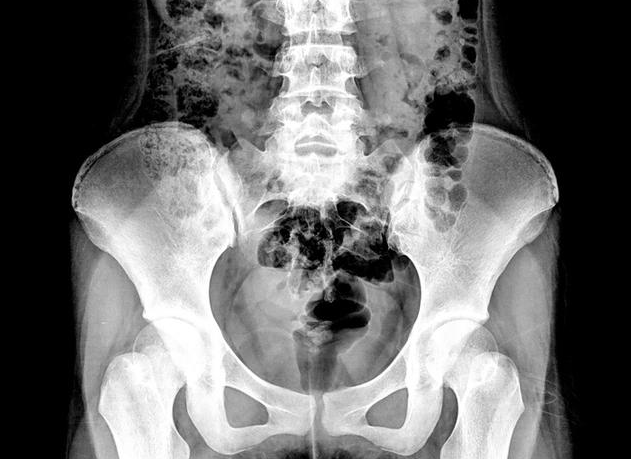

B超顯示盆腔積液并不一定就是盆腔炎的緣故,盆腔積液有生理性和病理性的,病理性的需要進一步檢查治療,那么,盆腔積液和盆腔炎有什么關系?B超顯示盆腔積液怎么回事?下面八寶網小編就來說說。

盆腔炎的盆腔積液一般是由于炎癥刺激腹膜滲出導致的,沒有滲出并不代表沒有盆腔炎。盆腔炎的診斷除了B超外,還要結合婦科檢查,排除其它婦科(子宮內膜異位癥、卵巢囊腫扭轉、黃體破裂、肌瘤變性等)或內外科的疾病(闌尾炎、腸道疾病等等)才能明確診斷。

盆腔積液本身并不是一種疾病,它只是B超影像學檢查的一種表現。具體的說,有些盆腔積液是生理性的,主要有排卵期的卵泡液,月經期的經血也可能逆流進入腹腔,這些盆腔積液,都是可以吸收的。